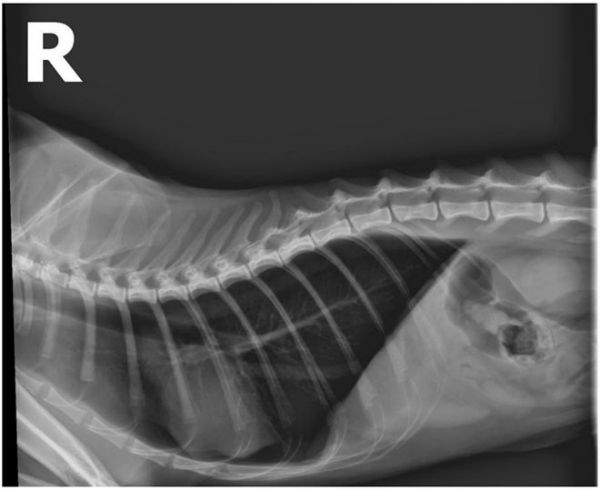

图7:住院第2天胸腔影像(左)

图8:住院第4天胸腔影像(右)

影像显示入院第2天时肺部渗出减少,仍存在少量胸水。第4天胸水有轻微增加,不过动物住院期间精神状态明显缓解,食欲好转,呼吸频率未见明显加快;黄疸消退,不排除入院时高胆红素血症是厌食引起的。入院第4天时因胸水有轻微增加,所以开始停止输液并进行利尿治疗,静推速尿8mg。

图10 胸腔侧位

12.1 胸腔X线

肺野清晰,肺静脉未见增粗,胸水消失。